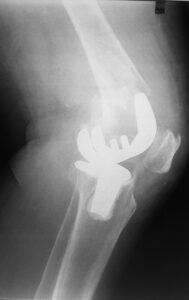

- Περιπροθετικό κάταγμα στην περιοχή του γόνατος , πολύ περιφερικό.

- Η ίδια ασθενής σε profile ακτινογραφία.

- H οστεοσύνθεση με ανάστροφη ενδομυελική ήλωση με πολύ μικρή τομή δέρματος.